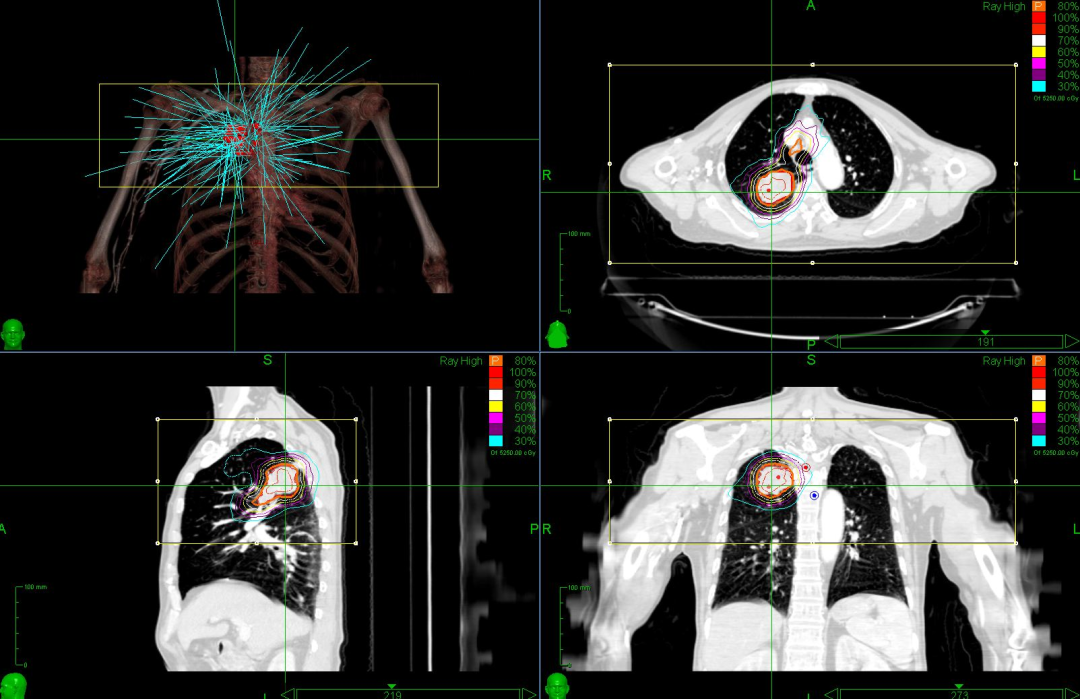

根据孙先生的情况,肿瘤科医师及放疗物理师为其量身定制了射波刀治疗方案。孙先生接受了射波刀治疗,整个过程不开刀、不出血。

射波刀治疗计划图

01、三维剂量雕刻式治疗,可根据患者体型、肿瘤部位、周围组织结构等因素,让射波刀的机器人手臂从空间1000多个入射角度中选择最优的角度进行剂量投照,再配合亚毫米级的走位精度可以实现非共面非等中心“剂量雕刻”式治疗,在提高了肿瘤剂量的同时,最大限度的保护了周围器官。

02、治疗前获取X射线图像,在治疗过程中进行实时追踪和修正。系统自动将获取的图像与定位图像进行关联并验证,产生的丝毫偏移将直接由机器人手臂自动修正,治疗精确度能够达到亚毫米。

03、根据不同部位的肿瘤靶区,提供个体化的追踪照射方案。比如针对肝脏、胰腺、肾脏、前列腺等部位肿瘤进行“金标追踪”,针对运动型脏器如肺部肿瘤,配合金标使用“呼吸追踪”或单独针对肺部肿瘤使用“肺部追踪”,针对脊柱及椎旁肿瘤进行“脊柱追踪”,针对头部肿瘤及上脊柱肿瘤使用“颅骨追踪”等。